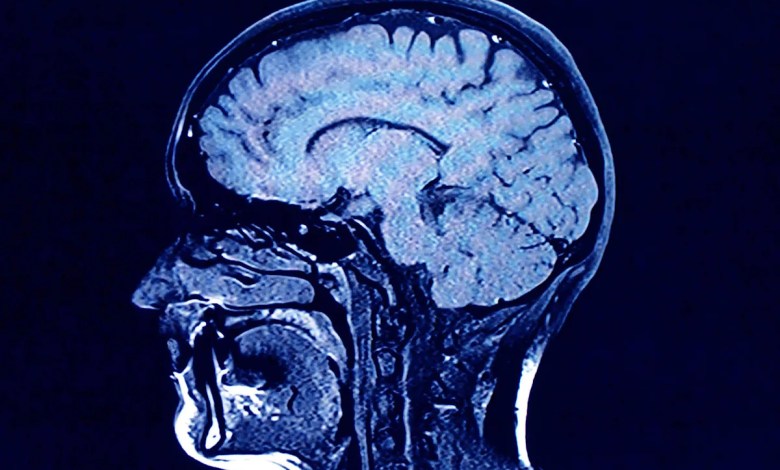

For their research, Mousley and his colleagues analyzed diffusion MRI scans — which are essentially images of how water molecules move in the brain — of about 3,800 people ages 0 to 90. The goal was to map the neural connections in the average person’s brain at different stages of life.

Based on MRI scans, the new study maps the average person’s neural network throughout their life, determining where connections strengthen or weaken. The five “epochs” described are based on the neural connections observed by the researchers.